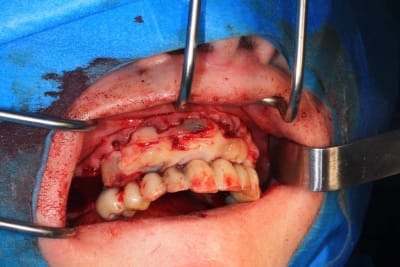

Le cas N°2 en images reelles :)

Guide métal avec support clavette, os assez fin : il est prévu un sticky bone complet : donc : lambeau avant extraction, positionnement du guide base et forage des clavettes, positionnement du guide implant, pose des piliers MU, controle des axes prothétique avec le guide pilier, collage des piliers prov sur le bridge a armature métal, occlusion nickel, sticky bone et PRF, sutures suspendues.

Ce qui ne vas pas : les dents un peu trop courte sur le provisoires, et le plan d'occlusion. L'erreur est de ne pas avoir utilisé Cadsmile3d pour le smile design du provisoire.

Ce n'est pas grand chose a prendre en compte pour le definitif.

Et surtout : j'ai creer une bonne courbe d'occlusion ideal, mais je n'ai pas imprimé de piste a coller sur son vieux stellite. Je vais rajouter de la résine samedi.

Mais tu peux me faire confiance.Le bridge prov était nickel, avec la clavette en place, sans que je ne doive meuler les puits préparés.

J’était vraiment content de n’avoir quasi aucune retouche d’occlusion.

Tu n'as pas bien lu le message au dessus. La courbe d'occlusion en haut est bonne. Normalement, on va modéliser et imprimer des cales que l'on colle sur le stellite.

Je n'allais pas faire des dents plus longues en haut pour avoir le contact avec un stellite affaissé.

Mais j'ai oublié de faire les cales. J'ai donc ajouté de la résine sur le stellite au controle des 3 jours. ( pas de photo ).